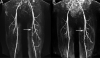

Methods: Sixty-eight patients with mild to moderate symptomatic PAD (age 65 ± 11 years; ankle-brachial index [ABI] 0.69 ± 0.14) were studied at baseline and annually for 2 years after beginning simvastatin 40 mg (n = 20) or simvastatin 40 mg/ezetimibe 10 mg (n = 18) if statin naïve, or ezetimibe 10 mg (n = 30) if taking a statin. Phosphocreatine recovery time was measured by (31)P magnetic resonance spectroscopy immediately after symptom-limited calf exercise on a 1.5-T scanner. Calf perfusion was measured using first-pass contrast-enhanced magnetic resonance imaging with 0.1 mM/kg gadolinium at peak exercise. Gadolinium-enhanced magnetic resonance angiography was graded. A 6-min walk and a standardized graded Skinner-Gardner exercise treadmill test with peak Vo(2) were performed. A repeated-measures model compared changes over time.

Figures